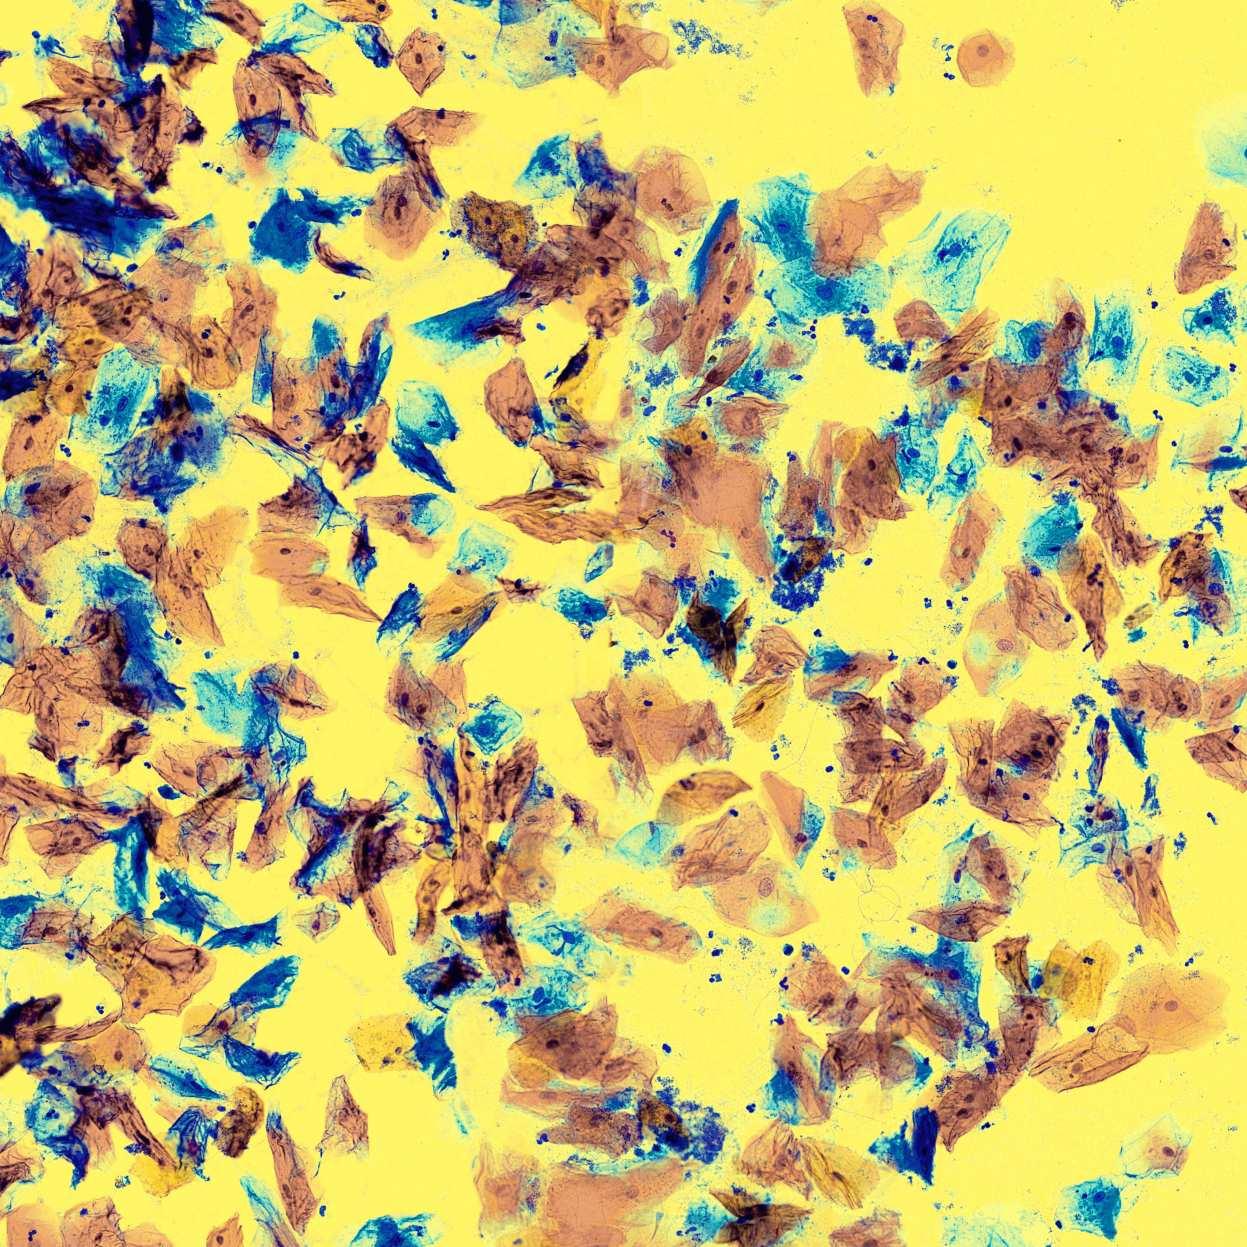

La coloration Papanicolaou est la coloration de référence utilisée en médecine pour différencier les cellules en fonction de leur maturité et de leur activité métabolique.

The Papanicolaou staining is the reference staining used in medicine to differentiate cells based on their maturity and metabolic activity.